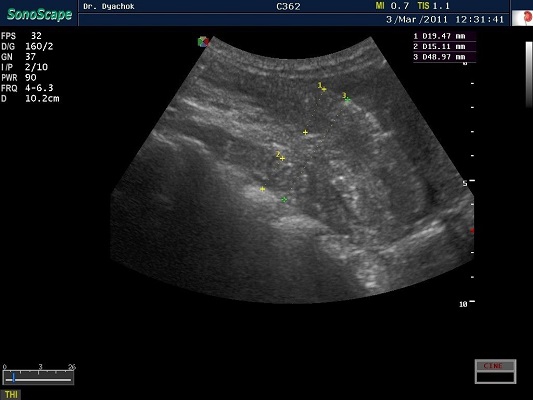

SonoScape S2N Vet – уникальная узи-система, выполненная в виде портативного ноутбука для легкой переноски. Отличается эта система цветным форматом визуализации, а также крайне чувствительными доплеровскими режимами, работающими на уровне премиальных аппаратов. При оптимальной цене – это очень хорошее и сбалансированное решение для ветеринарной клиники.

Диагональ монитора составляет 15,6 дюймов, что обеспечит комфортную работу для врачей и полный спектр визуализации для пациентов. Компактный вес не превышает 5 кг. (вместе с батареей), что оценят выездные бригады скорой помощи или ветеринары, выезжающие на дом.

Цифровая рабочая станция S2N Vet предполагает наличие жесткого диска для записи данных, составление и экспорт отчетов с возможностью добавления изображений, ведение базы данных пациентов.

Режимы сканирования SonoScape S2N Vet:

• В, М, В/М, В/В, 4В, Тканевая гармоника;

• Изменение масштаба изображения в режимах реального времени и стоп-кадра;

• Цветной, энергетический, направленный энергетический, импульсно-волновой,

• Постоянно-волновой допплер;

• Дуплексный, триплексный режимы;

• Трапецеидальное сканирование на линейных датчиках;

• Режим панорамного сканирования;

• Технология подавления спекл-шума MicroScan.